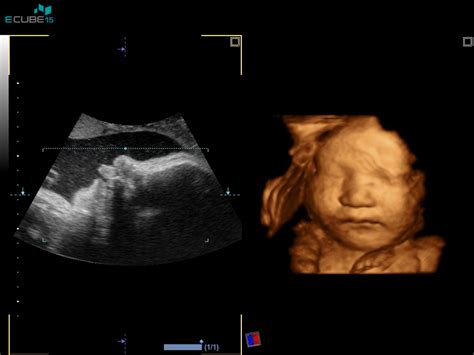

Nosečnost traja 40 tednov oziroma 280 dni, računano od prvega dne zadnje menstruacije. V 37. tednu ste že v zadnjem mesecu nosečnosti, natančneje v 37. tednu, kar pomeni, da je otrok že donošen in pripravljen na prihod na svet. Kljub temu se lahko porod začne kadarkoli med 37. in 41. tednom nosečnosti, saj le približno 5 % nosečnic rodi točno na predvideni datum. V tem obdobju se telo nosečnice intenzivno pripravlja na porod. Maternični vrat se skrajšuje, zmehča in se postopoma odpira. Otrokova glavica se lahko počasi spušča v medenico, kar lahko povzroči občutek pritiska navzdol in olajša dihanje.